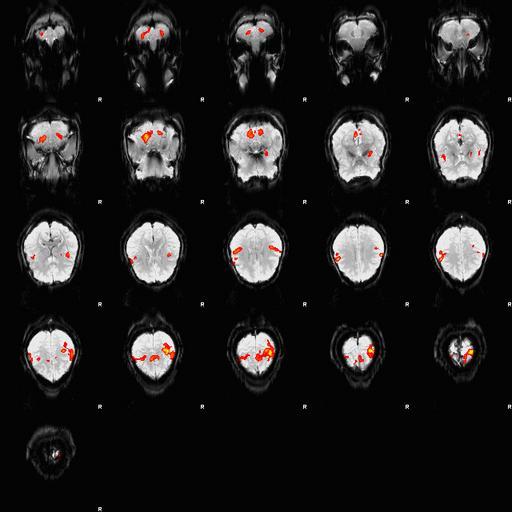

Keywords: Fingertapping experiment DXIII.jpg en An fMRI depiction of activated brain areas BOLD during an index finger-tapping sequence Experiment and imaging was performed in our dept at RIC at UTHSCSA Analysis for activation depiction was performed by me using fsl I used BET FAST and FEAT to obtain this image The experiment was performed in the following method Subjects performed a finger tapping sequence during a block design paradigm This study focused on only right hand unimanual index finger During the first 30 seconds the subjects moved their right index finger from side to side adduction-abduction at the rate of 2Hz followed by a 30 second rest period This sequence was repeated 6 times for a total of 6 minutes A Gradient-Echo planar sequence was used with the parameters of TR 2s TE 30ms and a flip angle of 90° and sixteen continuous 6mm-thick axial slices with an in-plane spatial resolution of 3mmX3mm I derived Own Zereshk This image was not published anywhere and was part of my class project Functional magnetic resonance imaging Sequence |